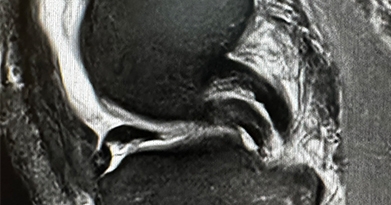

Arthroscopic Surgery

Arthroscopic surgery, is a surgical procedure to visualize, diagnose, and treat problems inside a joint using a specialized instrument known as an arthroscope. An arthroscope is a fiberoptic tube that contains a small lens or camera and a lighting system to magnify and illuminate structures inside a joint.